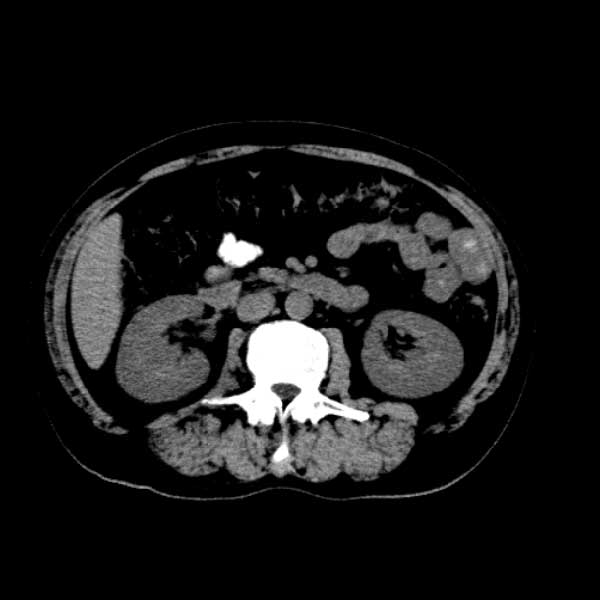

标题: CT13513:男 71 腹部疼痛20余天,近几天高热就诊,骨窗未见异 [打印本页]

标题: CT13513:男 71 腹部疼痛20余天,近几天高热就诊,骨窗未见异

考虑感染性病变可能性大,起源于阑尾?

感染,脓肿形成

考虑为化脓性阑尾炎.脓肿形成.及多肌肉累及.

考虑右侧腰大肌脓肿,向右髂窝、右腹股沟流注。

支持化脓性阑尾炎伴右髂窝脓肿、腰大肌腰方肌脓肿形成。

首先考虑化脓性阑尾炎伴腰大肌、腰方肌脓肿,不除外回盲部结核。

回盲部癌待排除。

患者肠镜检查考虑结肠癌,病理证实

患者肠镜检查考虑结肠癌,病理证实。肺部ct可见多发结节,考虑转移